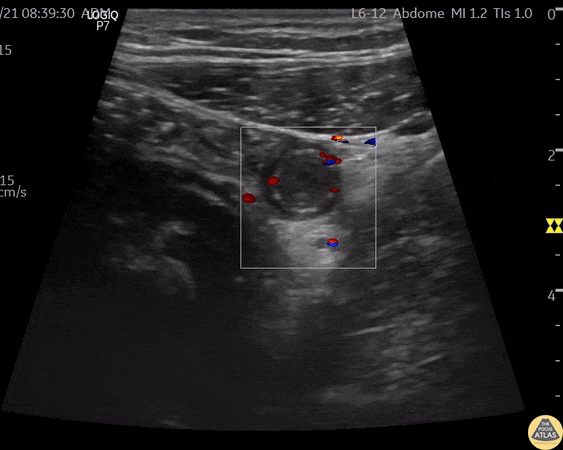

A 24 year old male comes to ER with abdominal pain, vomiting, and fever. A directed scan with a high-frequency linear transducer in the right iliac fossa shows a tubular, non-compressible structure, a "target like" image, with increased echogenicity of the fat around it. When applied Color Doppler - we can observe increased vascular flow around the appendix - a sign known as "The Ring of Fire". This finding suggests the diagnosis of acute appendicitis. Contributor: Renato Tambelli (@R_Tambelli @Jedipocus)